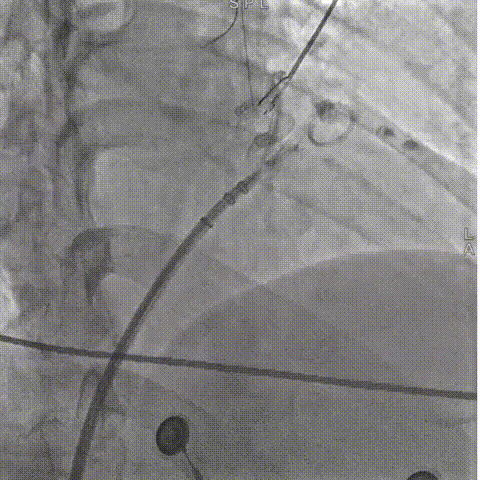

LAMax LAAC®2436 Plus封堵器封堵盘在DSA下牵拉15s,锚定伞稳定无移位。

牵拉实验,牵拉稳定无残余分流

符合COVER原则,将LAMax LAAC®2436 Plus封堵器释放,再次DSA造影检查,封堵器形态无变化,封堵效果好。

释放后封堵效果满意